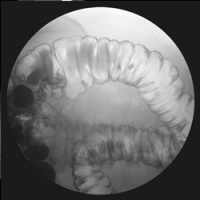

X-ray imaging is painless and has been in use since 1895. Medical uses of x-ray are many, ranging from imaging the skeletal system of bones, to imaging soft tissues such as lungs with chest x-rays, or intestinal or urinary system structures with contrast materials.

- Fluoroscopy, or real-time X-ray, allows the radiologist to view the body as it functions, making it possible to detect subtle abnormalities such as reflux or a hiatal hernia.